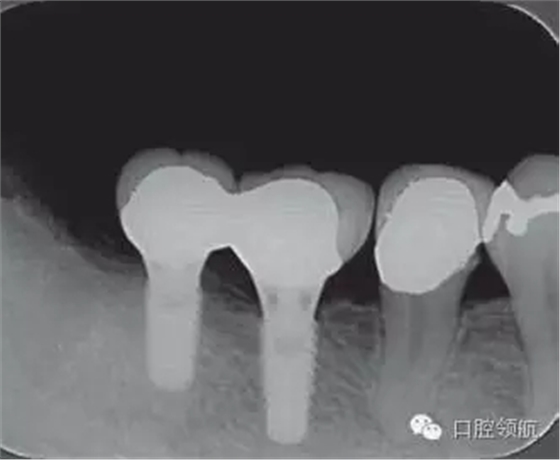

修復體安裝后的2003年1月復診時的X線片上,沒有發(fā)現(xiàn)種植體頸部有骨吸收現(xiàn)象,情況良好(圖2)。但是,2003年8月,因混合陶瓷樹脂部分修復體的破損而進行再制作時,發(fā)現(xiàn)有輕度的咬合疼痛以及舌側(cè)頸部的牙齦有輕壓痛??趦?nèi)沒有觀察到該部位的牙齦紅腫。X線片可以觀察到(左下第6顆牙) 的種植體頸部有達到第4螺紋的骨吸收現(xiàn)象(圖3)。

圖2 沒有發(fā)現(xiàn)種植體頸部的骨吸收(2003年1月)